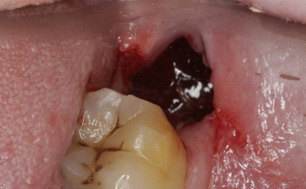

目前认为干槽症是牙齿拔除后由口腔细菌所引起的骨创感染。拔牙窝空虚和感染是其产生的主要原因。正常的拔牙窝愈合是牙齿拔除后,血块充满拔牙窝后形成了高质量的充填物,凝固后保护拔牙窝,促进伤口的愈合。而在愈合过程中,如果凝血块脱落或者感染,就可能导致干槽症。多发生于下颌智齿拔除后。

典型的症状是:拔完牙3~4天后出现剧烈的疼痛,疼痛向同侧耳朵、太阳穴处放射,口服止痛药不能缓解。